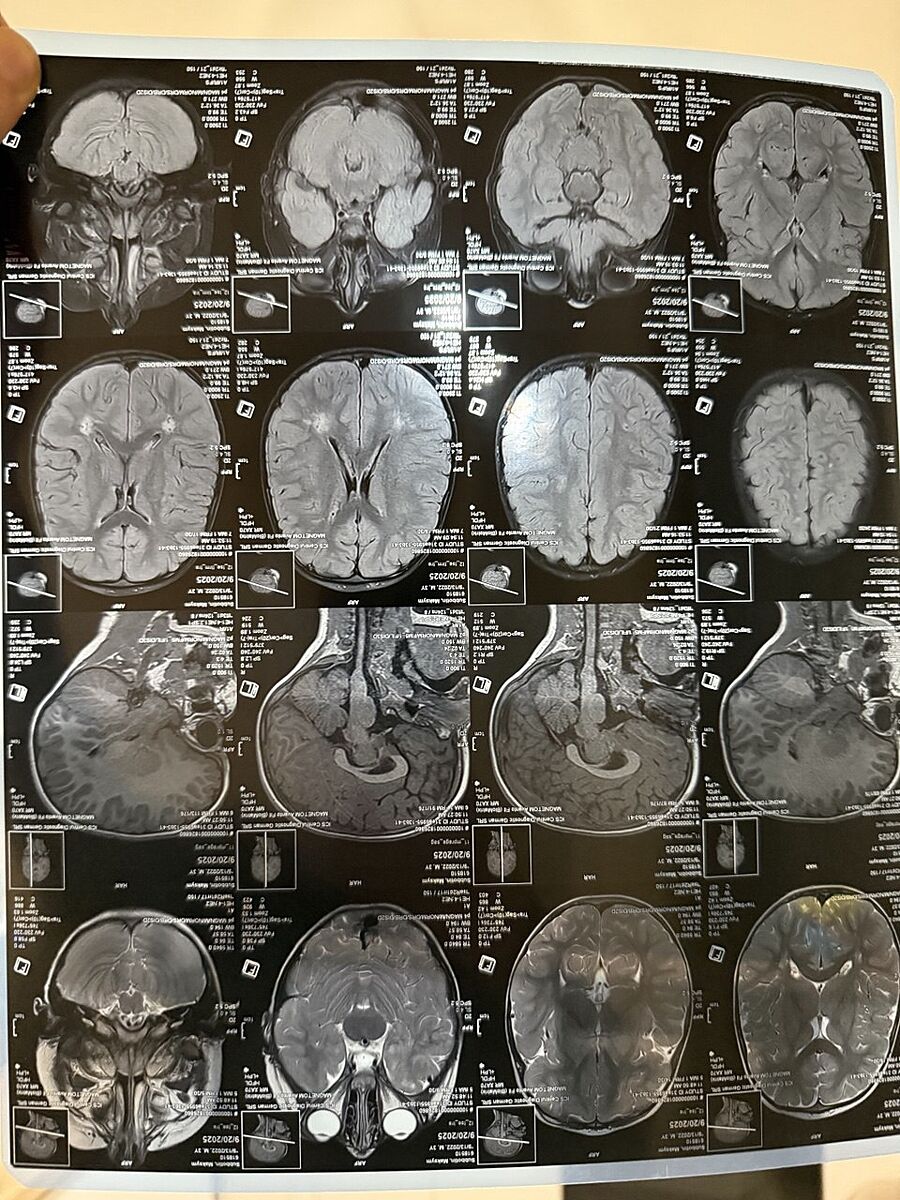

Мрт головного мозга ребенка, белые точки это глиозные изменения. 2 невролога мне говорят не паниковать, логопед-дефектолог в помощь, садик, назначают ноотропы ( вижу результат) каковы шансы выйти в норму?

Гліоз є наслідком . Часто це випадкова знахідка на Мрт , яка не несе нічого . Також ці зміни можуть впливати на мову, розуміння мови( якщо осередок у лобній та скроневій долі)

Так и есть, следствие гипоксии, мне так и написали в заключении